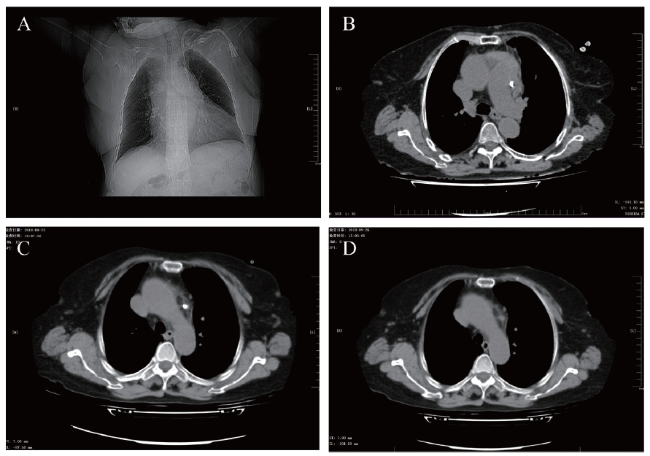

术后行胸部CT检查示留置导管影末端位于左肺动脉旁,左颈前、纵隔区密度显著增高,并见絮片状高密度影及气体影,CT值约35 Hu,边界不清,可能为积血及积气(图1A、B)。考虑导管末端已穿出左颈内静脉,进入纵隔可能性大,经导管动脉端注入少量低浓度碘氟醇造影剂行数字减影血管造影(DSA)检查,提示导管末端位于中纵隔内,未进入动静脉、心包腔。急请心血管内科、心胸外科、普外科会诊,考虑若现在拔管,左颈内静脉内血液有进入破口处致局部血肿或大出血压迫纵隔内组织、器官引起严重并发症等风险,甚至可能需手术止血。如果待2 ~ 3周导管末端局部血肿凝固、机化后行拔除留置导管,有利于局部止血和降低拔管风险。综合考虑选择待2 ~ 3周再拔管。等待拔管期间予以监测患者血压,定期复查血常规、肾功能、电解质,治疗上予以注射用矛头蝮蛇血凝酶2 U肌肉注射3 d避免出血、硝苯地平缓释片控制血压、重组人促红细胞生成素改善贫血,期间患者血常规未见明显改变、无明显电解质紊乱、血清肌酐值较前有所下降,予以暂缓血液透析治疗。

图1 一例左颈内静脉置管误穿纵隔患者的CT图

A:导管尖端平第4胸椎下缘左侧;B:导管尖端位于肺动脉干旁,周围可见血肿稍高密度影;C:第20日见主动脉弓旁血肿密度降低;D:拔管第2日未见主动脉弓旁新发密度影

9月25日行胸部CT示中纵隔区脂肪密度略模糊,见少许絮状高密度影,边界欠清,可能为积血,与2018年9月6日胸部CT比较病灶明显减小;双肺少许炎症,右侧叶间积液;心脏增大,心包少量积液(图1C)。据患者胸部CT结果,提示导管末端局部血肿已凝固、机化,决定于超声引导下拔除左颈内静脉留置导管,请胸外科、普外科、B超科协助,患者平卧位,予以心电图、血压、血氧监测,拔除导管并行局部加压15 min。术后即行彩超检查示导管经左颈内静脉至左头臂静脉与左锁骨下静脉交汇区刺破血管进入纵隔处未见血液。拔管后患者生命体征平稳,观察30 min后平车返回肾内科。术后复查血常规、肾功能数值基本同前,术后24 h复查胸部CT示纵隔内未见新发高密度影(图1D)。